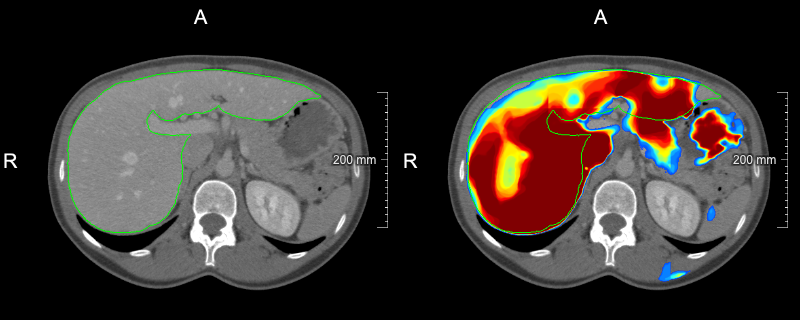

Refer to caption

(a) slice-level uncertainty: 0.0660.0660.066

(b) slice-level uncertainty: 0.0560.0560.056

(c) slice-level uncertainty: 0.0520.0520.052

(d) slice-level uncertainty: 0.0200.0200.020

Figure 2: Examples of slices selected in the first USS iteration with overlaid liver reference segmentation (green contour) and model liver probability output (heatmap): (a)-(c) slices with the biggest slice level uncertainty, (d) slice with the lowest uncertainty among selected ones.

As our strategy relies on the model’s uncertainty to query cases, the confidence calibration of a model can have a substantial impact on which cases are deemed uncertain. Recently, it has been shown that modern deep neural networks do not output well-calibrated probabilities and tend to be overconfident[28]. In our work, we have used MC dropout that improves the calibration quality of models trained with the Dice loss[22]. Exemplary probability maps produced by our model are shown in Fig. 2. We think that investigation of various calibration techniques, e.g., deep ensembles and temperature scaling, in the context of active learning could be an interesting future research direction.